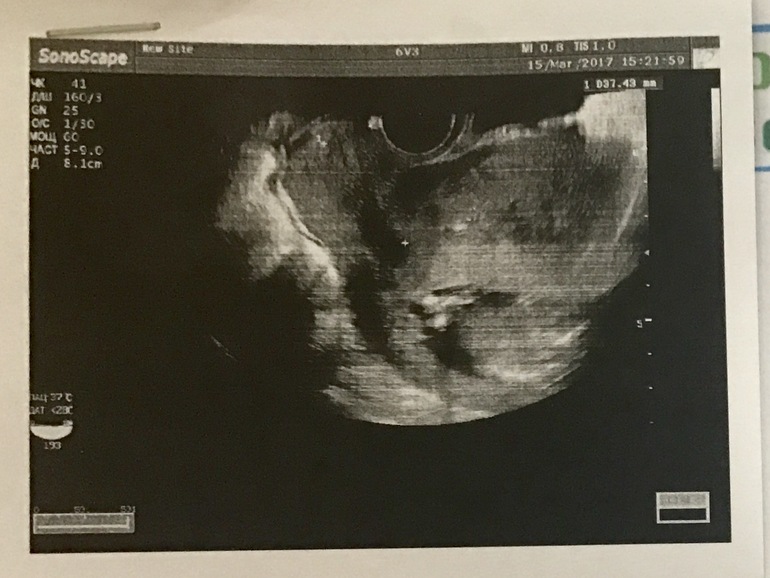

Сегодня срочно нужно было сходить на УЗИ не к своему доктору (вчера упала)

Смотрели вагинально. Попросила глянуть пол малыша. Слышала про доктора, что она глазастая узистка и знакомым пол ребёнка говорила чётко в 12 недель. Я так ждала , она вертела, вертела, а потом сказала, что видно плоховато (не знаю почему именно) но больше похоже на девочку, чем на мальчика.

Дала распечатку фото, но я понятия не имею что это вообще как на нем.

И глазастых прошу рассмотреть записи в левом углу. Там в конце есть параметр Д -8,1см, это длина ребёнка? Или это данные датчика этого))) Полностью или КТР? Она так быстро все делала и улетела. Я мало что поняла. Главное конечно, что кроха здоров и у меня все хорошо. Сердечко 142 удара)

В правом нижнем углу 3,48 ,по-моему.цифры нечетко видно.это длина шейки матки

Добрый вечер.на фото шейка матки.стенки матки.плацента по передней стенке.попа малыша и косточки ножек

Только попы не вижу. Это наверное, косточки ножек в тёмном пятне, в центе чуть правее, да?)

Беленькая палочка и кружочек это бедрышко и коленочка.